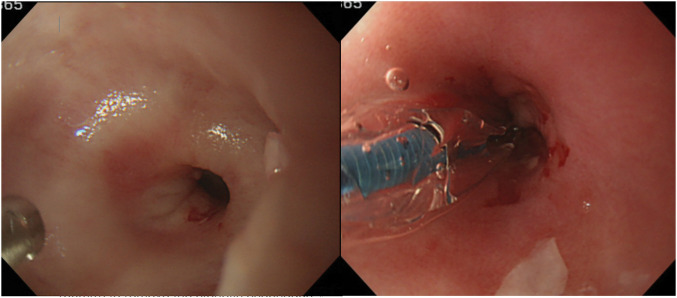

Case presentation: The patient was a 67-year-old man who was diagnosed with esophageal achalasia 13 years earlier. Partial esophagectomy of the portion with the stricture and esophago-jejunal anastomosis using the overlap method were performed for the esophageal stricture due to rupture during endoscopic balloon dilatation. The patient's postoperative recovery was unremarkable, and the dysphagia due to esophageal stricture disappeared.